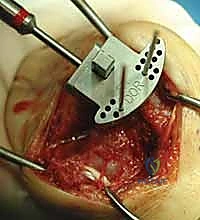

Carpal preparation requires exacting precision. Using the Maestro system as the archetype, the carpal resection guide is positioned to allow resection of 2 to 3 mm of the capitate head. It is provisionally held in position with two 0.062-inch Kirschner wires. The first wire is placed into the capitate neck and the second into the metaphysis of the third metacarpal, ensuring that the guide is perfectly parallel to the third metacarpal axis. With proper placement, the ulnar guide wing will lie close to the triquetrum–hamate articulation, and the radial wing will bisect the scaphoid at its distal third.

With the wrist held in neutral, the radius is scored through the cutting slot in the guide to provide a reference for the distal radial resection. The thumbscrew on the carpal resection guide is loosened to allow insertion of the radial resection guide boom. Following radial resection, the scaphoid, capitate head, hamate edge, and triquetrum are resected at a precise 90-degree angle to the axis of the forearm jig. The trial carpal plate is provisionally determined by the curvature and width of the remaining proximal carpal surface; it must lie flush with the hamate and proximal capitate surfaces. Unlike older designs, it is not always necessary to attempt fusion of the distal pole of the scaphoid to the surrounding carpus. The Maestro Wrist has a provision to replace the entire scaphoid using a carpal plate incorporating a modular radial augment, of which three separate sizes are available.

Following capitate reaming, the chosen carpal plate and stem are assembled and inserted into the capitate and seated onto the resected carpal surface. The carpal plate is anchored to the carpus with a radial screw that optimally does not penetrate the second metacarpal, and a second screw placed ulnarly into the hamate. This construct ensures stable distal fixation while avoiding the deleterious lever arm of a long metacarpal stem. Trial reductions are performed to assess stability, range of motion, and impingement. Once kinematics are confirmed, the definitive ultra-high-molecular-weight polyethylene (UHMWPE) body—which is direct compression molded onto a cobalt chrome alloy radial body—is impacted. The capsule and extensor retinaculum are meticulously repaired to prevent extensor tendon bowstringing and provide a robust soft tissue envelope over the implant.

Clinical & Radiographic Imaging Archive